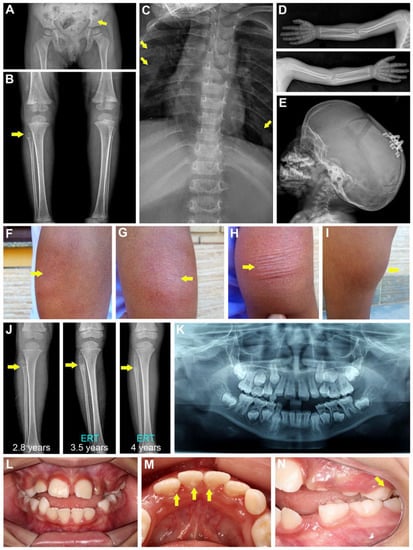

The proband is an eight-year-old girl, the second child of non-consanguineous parents. There is no history of skeletal anomalies in her family, including in her older sister. The proband was evaluated at 11 months of age because of motor developmental delay and failure to thrive. A physical exam showed a weight of 6800 g (Z-score, −2.07), length of 65 cm (Z-score, −2.48), and occipital frontal circumference (OFC) of 46.5 cm (Z-score, 1.42). The dolichocephalic skull had no facial dysmorphisms, and the patient had a pectus carinatum with a bell-shaped thorax. The skeletal survey disclosed abnormal, heterogeneous trabecular bone in the ilium bone of the pelvis, proximal femur, and the long bones at the knees, with radiolucent areas in the proximal metaphysis of the fibula and in the central metaphysis and epiphysis of the left distal femur (Figure 1A,B). The proband showed enlargement of the anterior costochondral junction (Figure 1C). No abnormalities were observed for the long bones of the upper limbs (Figure 1D). A 3D computed tomography scan of the skull disclosed premature fusion of the sagittal and metopic sutures and a partial fusion of the lambdoid sutures, requiring surgical correction at 23 months of age (Figure 1E).

Figure 1.

Clinical presentation. Representative radiographs of the proband at 2 years of age show (A,B) abnormal heterogeneous trabecular bone in the ilium (yellow arrow in A), proximal femur, and the long bones at the knees, and radiolucent areas in the proximal metaphysis of the fibula (yellow arrow in B) and in the central metaphysis and epiphysis of the left distal femur. (C) The proband shows enlargement of the anterior costochondral junction (yellow arrows). (D) No abnormalities were observed for the long bones of the upper limbs. (E) Note a dolichocephalic skull and the presence of distractors after cranial vault decompression. (F–H) Asfotase alfa ERT was associated with injection site skin reactions including redness, swelling, and thickening (yellow arrows indicated affected regions) and (I) lipodystrophy, as shown in this photograph of the proband’s thigh. (J) The radiolucency and traverse fracture detected in the proximal right fibula (white arrows) were resolved after introduction of asfotase alfa ERT, with follow-up images at 3 years and 5 months and 4 years. (K) Panoramic oral radiograph of the proband at 8 years of age shows a mixed dentition. (L–N) Intraoral photos at 8 years of age show mild enamel hypoplastic lesions on the lower permanent incisors and upper deciduous left molar (yellow arrows).

ERT with asfotase alfa was administered subcutaneously to the proband (2 mg/kg; 3×/week) starting at the age of 2 years and 10 months. ERT resulted in improvement in her pain and anthropometric measurements, as well as her gait and motor skills, though these lagged compared to the motor achievements of her peers. In addition, bone mineral density (BMD) (total body and lumbar spine (L1–L4)) was periodically obtained after the first year of ERT by dual-energy X-ray absorptiometry (DXA), and data analysis showed BMD Z-scores within the normal lower range for both total body and lumbar spine, ranging from −3.4 (at the age of 3 years) to −2.9 (at the age of 7 years). During the first six years of ERT, the proband experienced some mild skin reactions such as redness, swelling, and thickening (Figure 1F–H). More recently, she developed lipodystrophy at injection sites, mainly in her thighs and arms (Figure 1I). The radiolucent anomaly detected at the proximal right fibula, and a transverse fracture in the proximal fibula diaphysis, showed substantial resolution after initiating ERT, based on follow-up radiographs at 3 years and 5 months and at 4 years of age (Figure 1J). No recurrent bone fractures occurred after initiation of ERT, but the proband has complained of occasional pain in the lower limbs. The Z-scores of her weight and height before the ERT (at 2 years and 3 months) were −2.84 and −2.07, respectively. These improved to −1.50 and −1.47, respectively, at the age of 3 years and 5 months, after 7 months of ERT. Currently, her weight is 28 kg and height is 1.20 m (Z-scores, 0.04 and −1.86, respectively).

A detailed dental assessment was not performed until the proband was eight years of age. Oral examination revealed areas of mild enamel hypoplasia and an accelerated exfoliation of deciduous teeth, including canines and molars (Figure 1K–N). The proband exhibited good oral hygiene with a plaque index of 26% and bleeding index of 28%, no signs of gingival recession, and no pathological swellings. Periodontal probing showed normal attachment levels and no sign of periodontal pocketing due to alveolar bone loss (data not shown). Upon collection of medical/dental history information, the proband’s mother recalled that eruption of her first teeth was delayed, occurring at 16 months of age. Two deciduous mandibular incisors were prematurely lost with intact roots at the age of three years and six months. In addition, the proband’s maternal great grandmother reportedly lost permanent teeth at a young age (30 s).